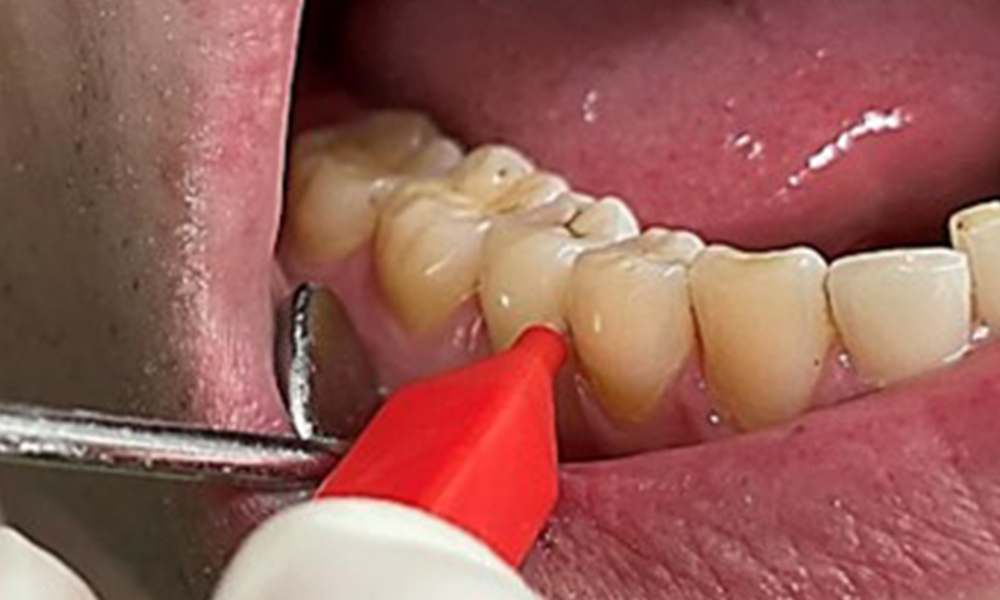

Discolouration caused by nicotine and tea consumption can be removed easily using an air polisher (Fig. 11).

When using more abrasive powder, it is essential to work from a cervical to coronal direction and never point the outlet nozzle towards the gingiva to prevent potential emphysema. Good suction on the contralateral side is essential to reduce aerosol formation (Fig. 12).